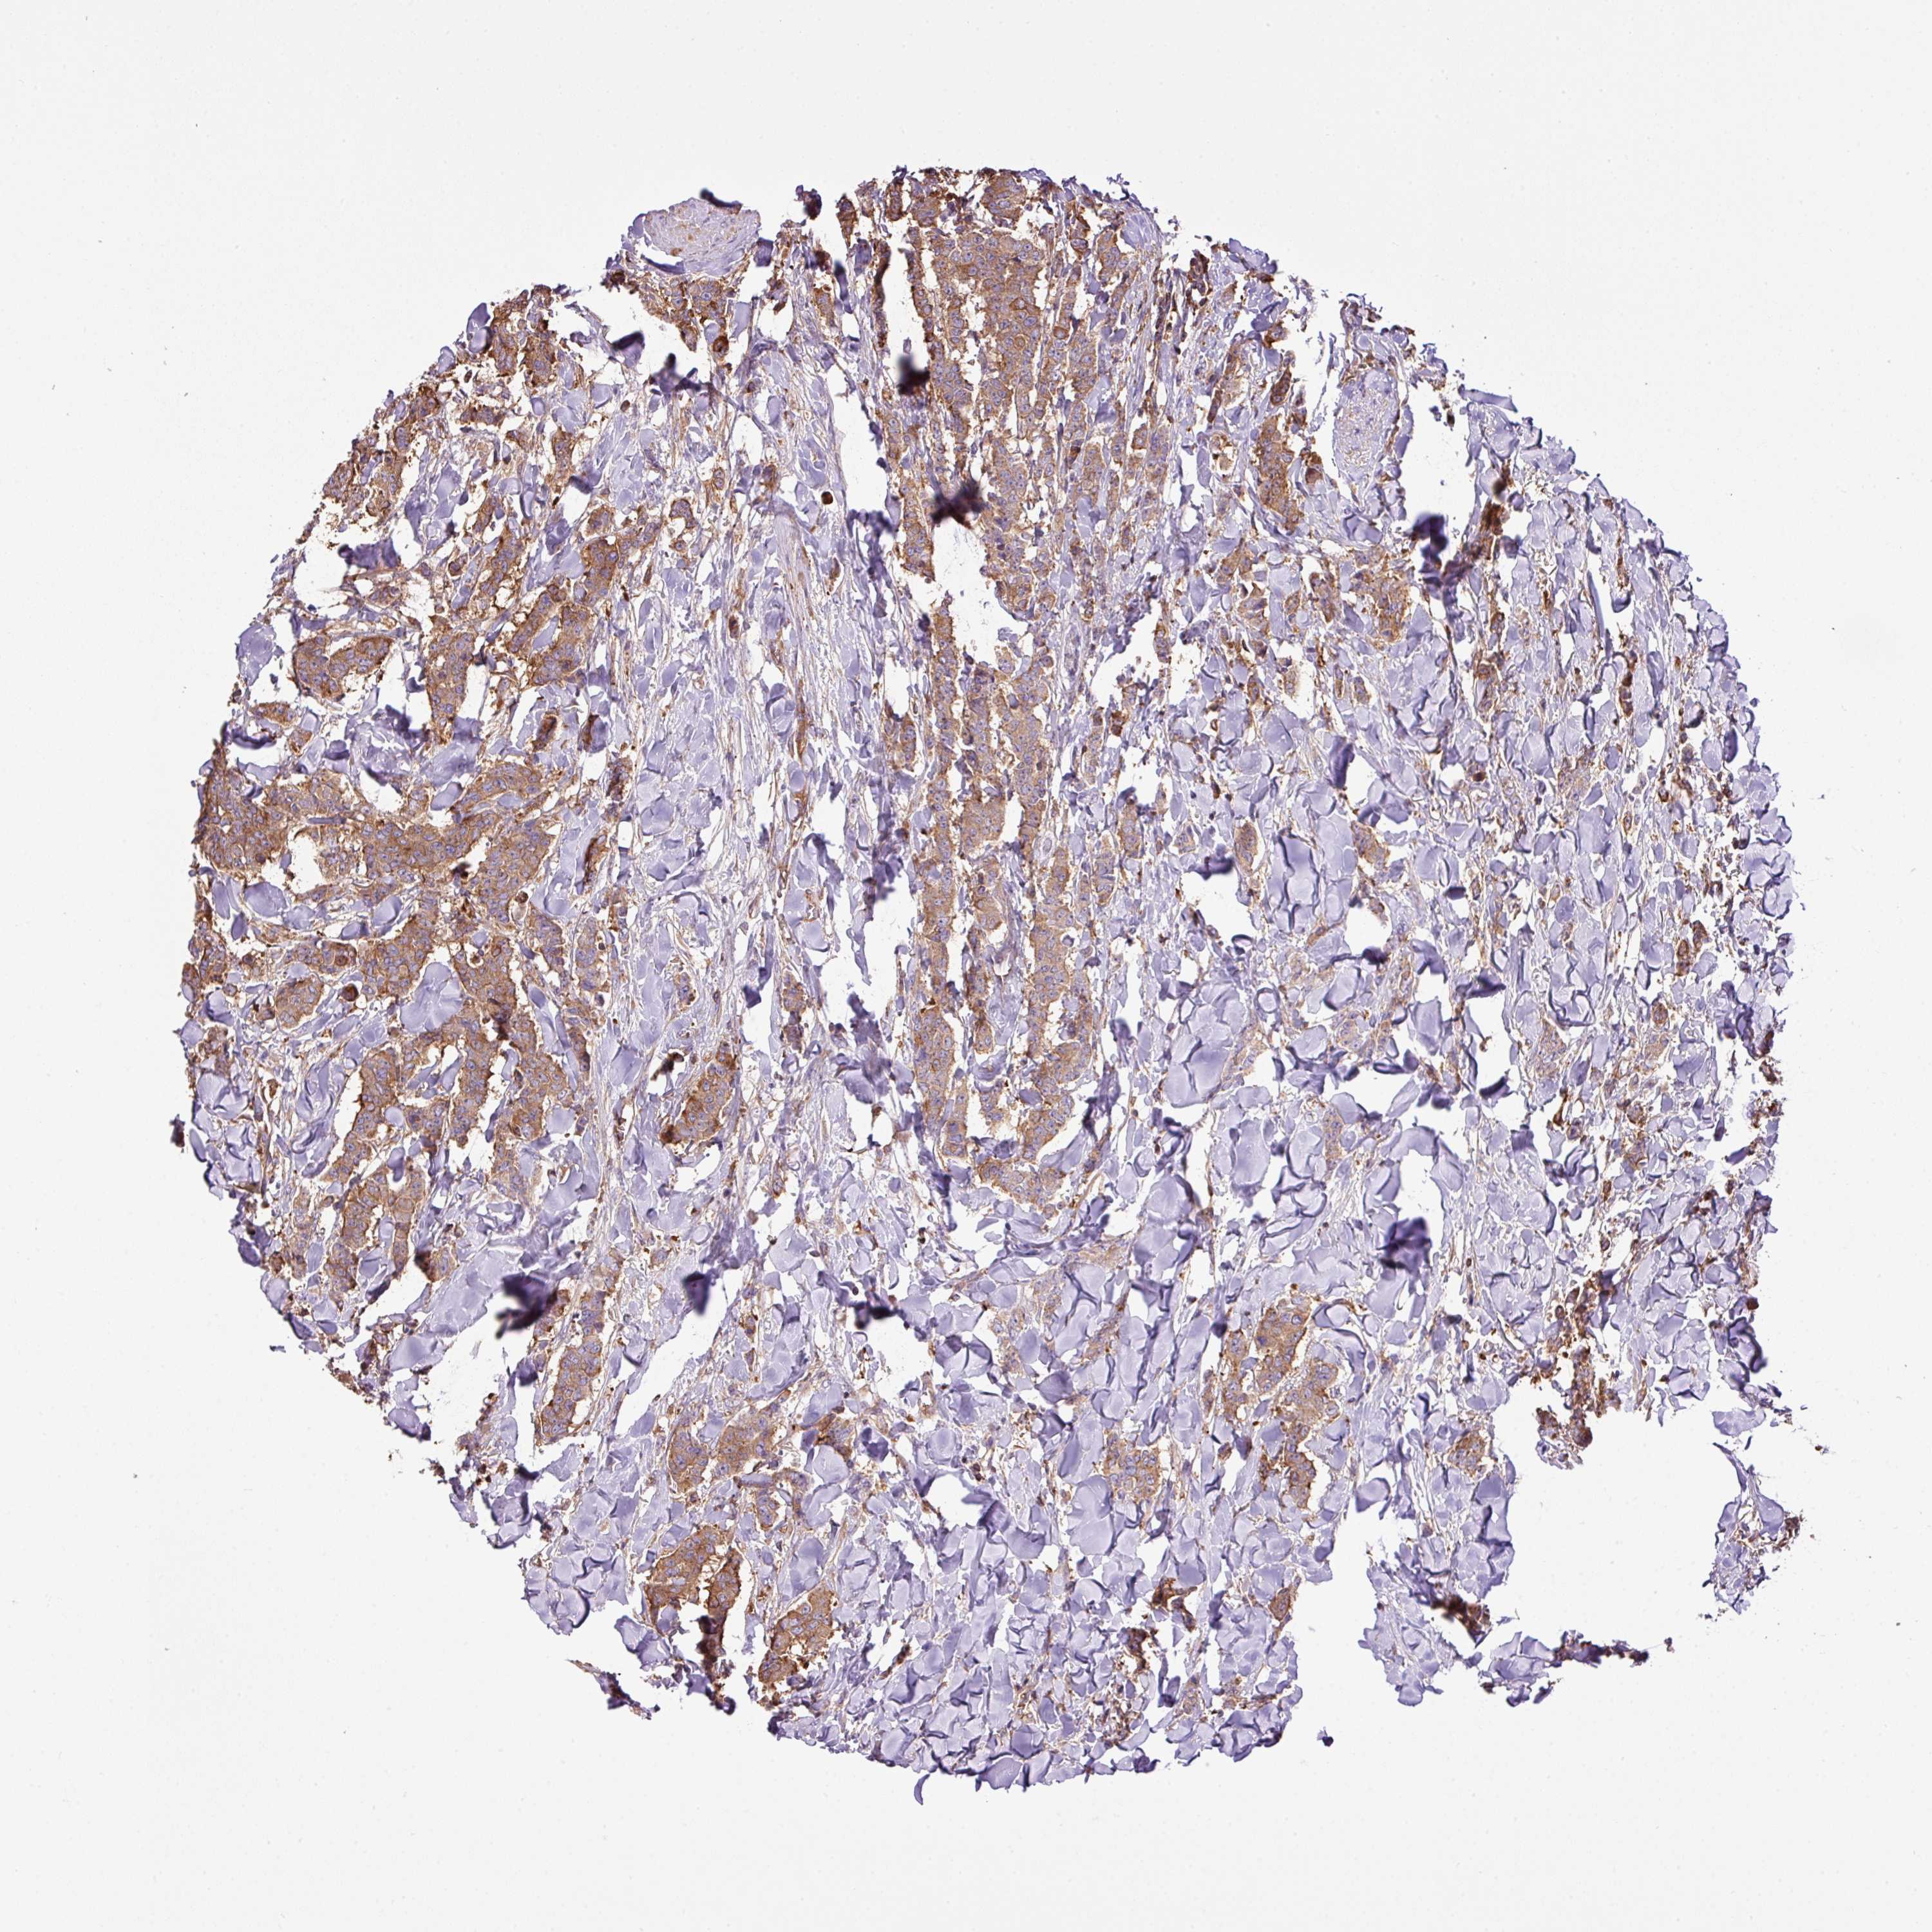

CANCER BREAST CANCER Show tissue menu

BRCA TCGA BRCA VALIDATION PROTEIN EXPRESSION